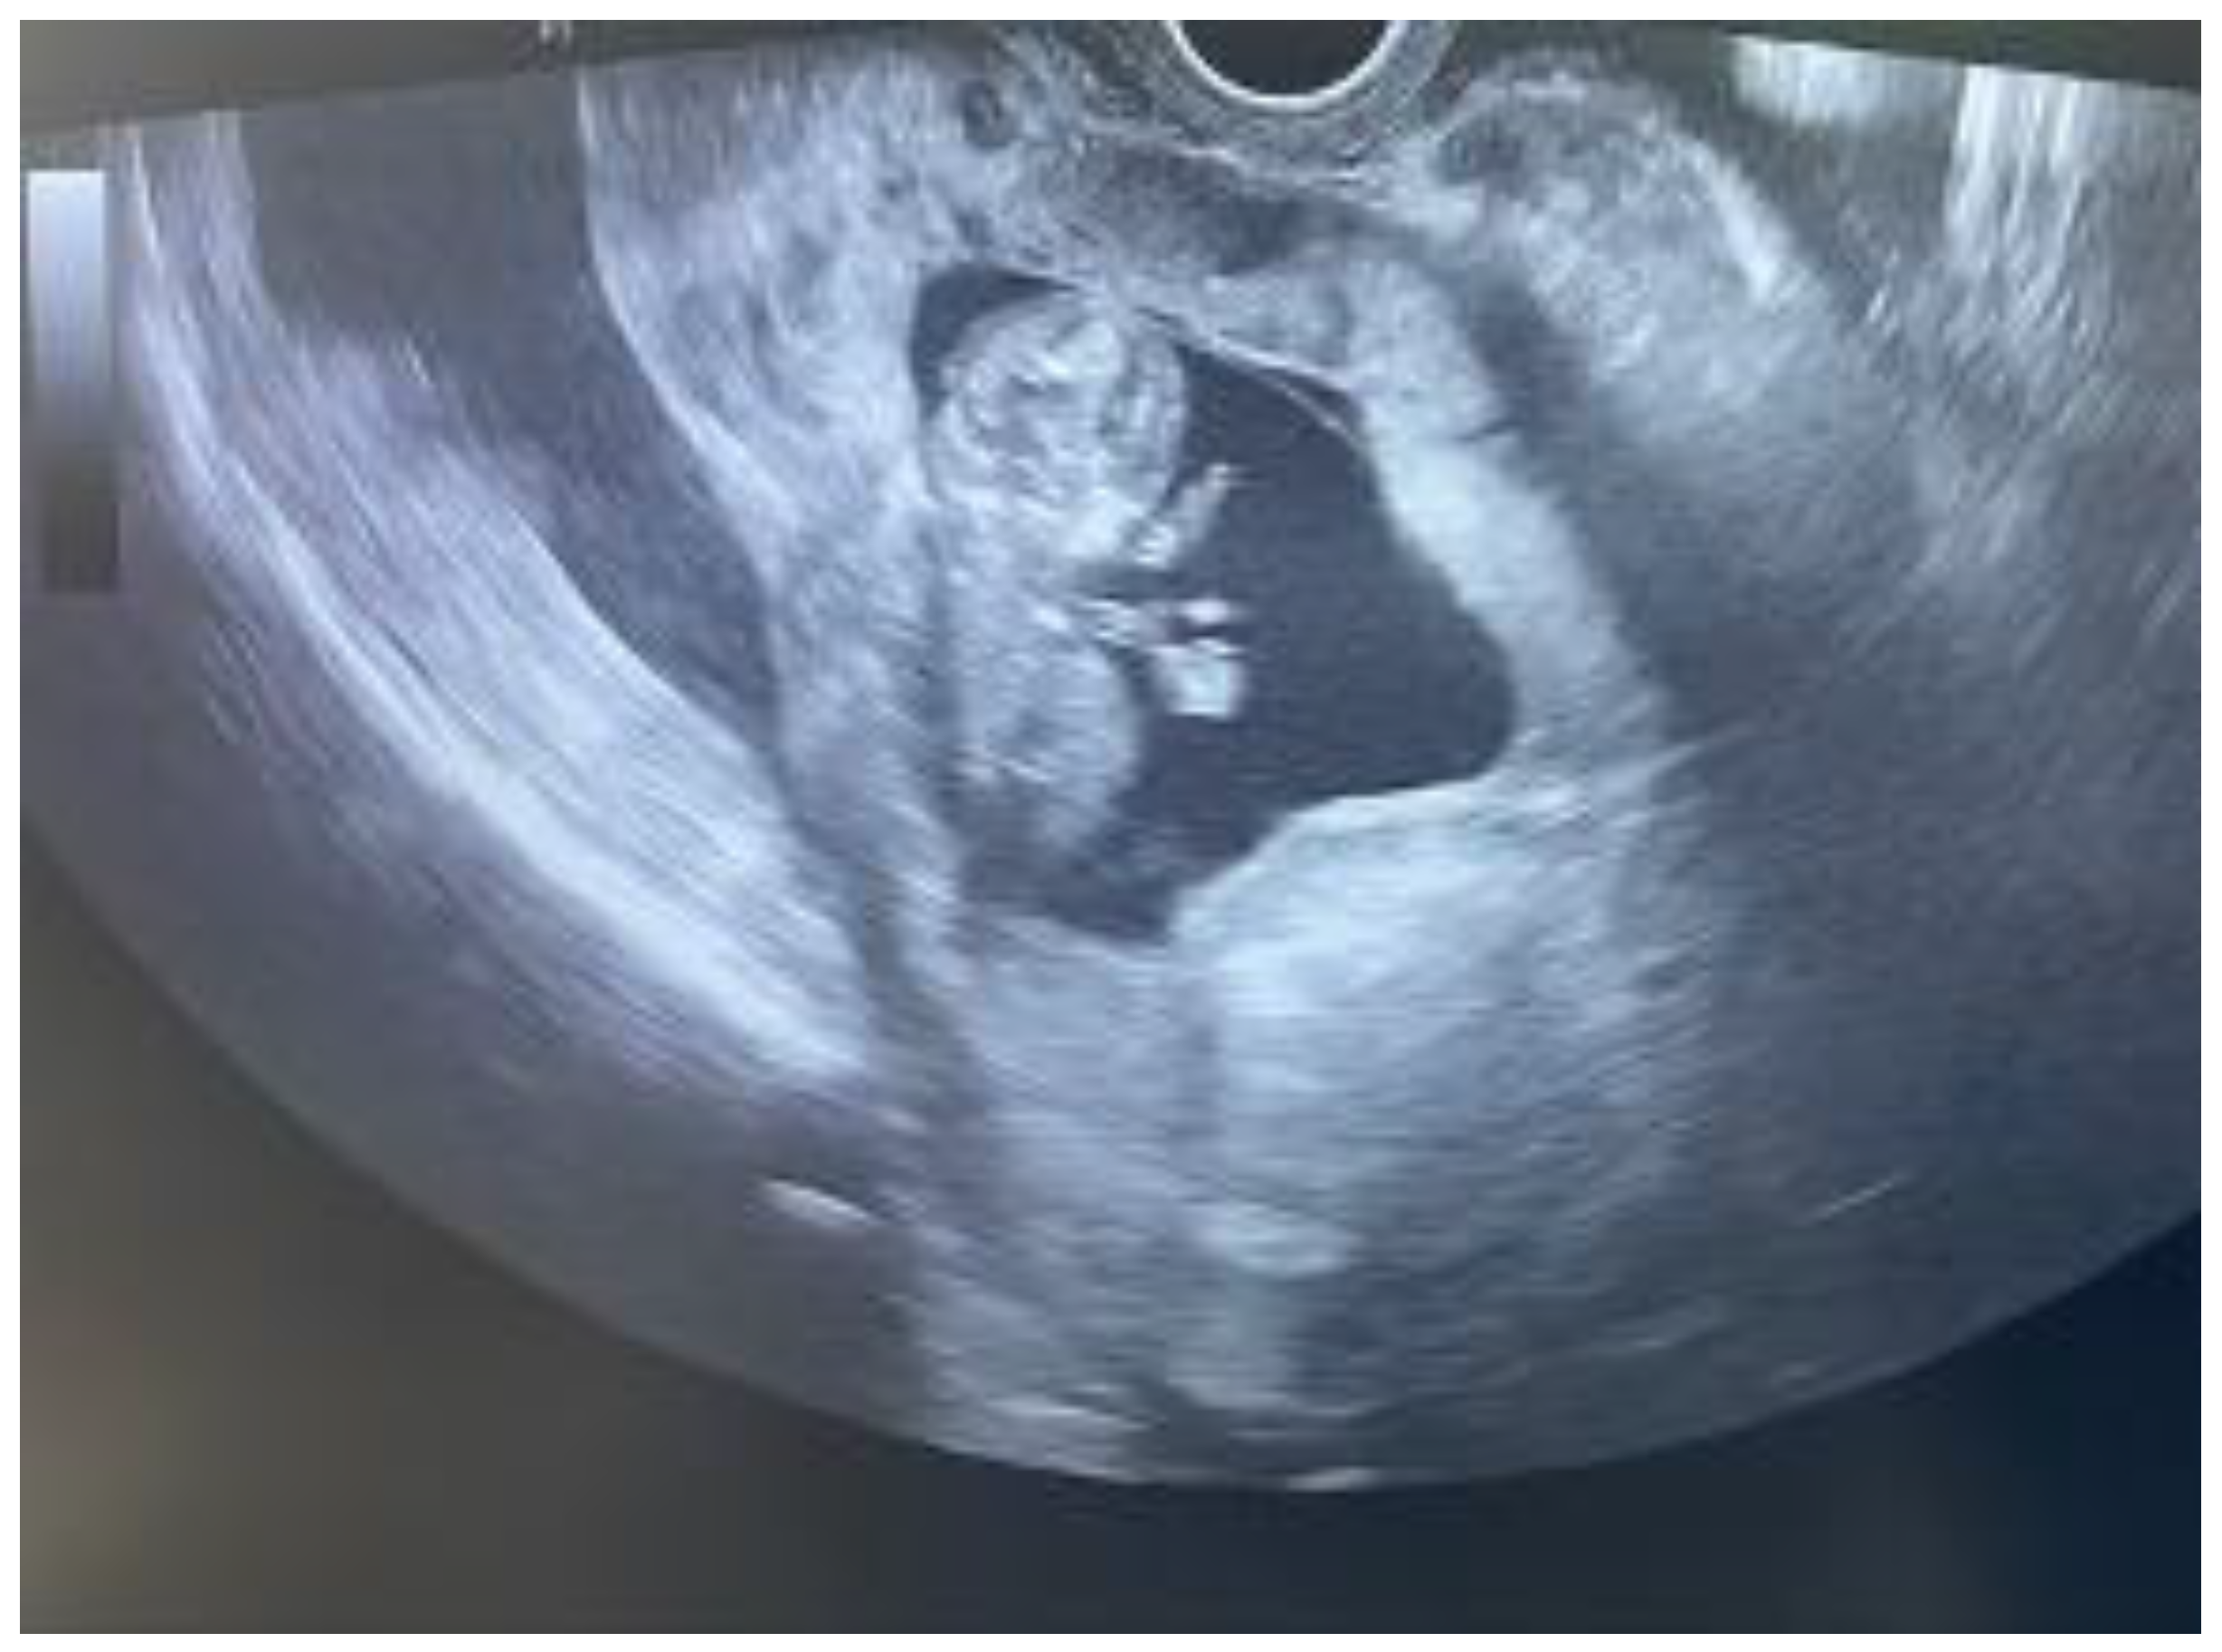

| Our case | lower diffuse abdominal pain and syncope | Intrauterine pregnancy with cardiac activity; free fluid next to the liver and in the pelvis; placental tissue on the anterior uterine wall; no myometrium or serosa at the level of the C-section scar | C-section scar UR | yes |